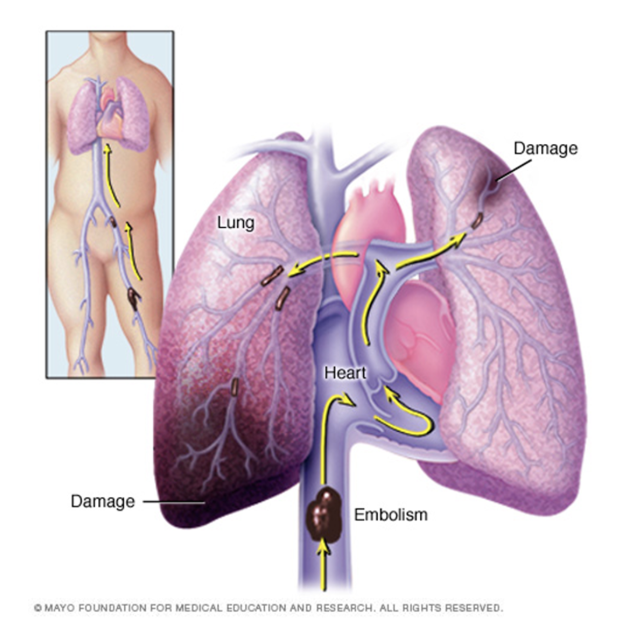

pulmonary embolism

blood clot, fat, septic, amniotic fluid in lungs

usually originates from lower extremity DVT

acute (new obstruction that requires immediate tx) vs chronic (older obstruction that has not been resolved; can worsen over time → pulm HTN → R HF )

massive PE → shock, severe pulm HTN, cardiac / resp arrest

mortality rate 30-60%

>50% of pts have NO sx

dx: D dimer (positive = clot that’s beginning to break down), ultrasounds, VQ scan, CT angiogram, pulm angiogram, MRI

tx: anticoagulation, thrombolytics, embolectomy, ventilation → SMALL TIDAL VOLUME AND LOWER PEEP b/c do not want to press emboli to brain